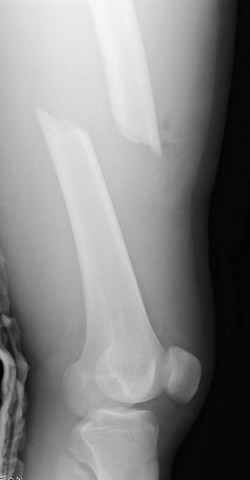

33 yo male motocross rider crashed after a jump sustaining isolated bilateral femur fxs, R side with a basicervical femoral neck and ipsilateral mid-distal 1/3 shaft, L side with a subtroch/prox 1/3 femur fx. Pt was HD stable, no LOC, GCS - 15, No other injuries, spines cleared.

Sequence ­ Right neck, right shaft, then left shaft.

Implants ­ plenty of opinions exist for the right side...some would use neck screws anteriorly after reduction, then with a slender reamed locked nail

pushed in behind the neck screws for the shaft... some will advocate a recon nail for both...some will use a sliding screw for the neck then a retrograde shaft nail...some would use the sliding neck screw and a shaft plate also...lots of options.

I prefer excellent neck reduction either closed or open, screws high and low anteriorly for it, then a frail locked nail slipped in behind the neck screws for the shaft.

basicervical neck is normally treated with hip screw or cephalomedullary nail.

after perfect reduction (either closed or open) i would attempt 1 implant to treat both (i.e. TFN or Intertan). can do anything though like Dr. Routt mentioned. intertan is nice because of the rotational stability it imparts in the neck

Chip Routt listed all main options. The right proximal fracture looks closer to trochanteric. Most elegant solution would be to fix all with a single implant with minimal incisions. Long Gamma nail or any other reconstruction or proximal type nails are suitable. Technically less demanding wiuld be temporary neck pinning as is, retrograde nailing of the shaft, then final reduction and fixation of the trochanteric fracture as isolated, by DHS with 2 holes plate. Good luck.